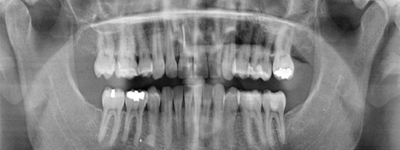

El escáner dental 3D captura imágenes detalladas de la boca, permitiendo una representación tridimensional de los dientes y las estructuras circundantes. Estas imágenes precisas se utilizan para el diseño y fabricación de piezas dentales

Implantología

La fresadora dental, en combinación con el escáner más el software de diseño digital de prótesis dentales, son nuestras herramientas más exactas y detalladas para realizar prótesis dentales de máxima precisión y estética.